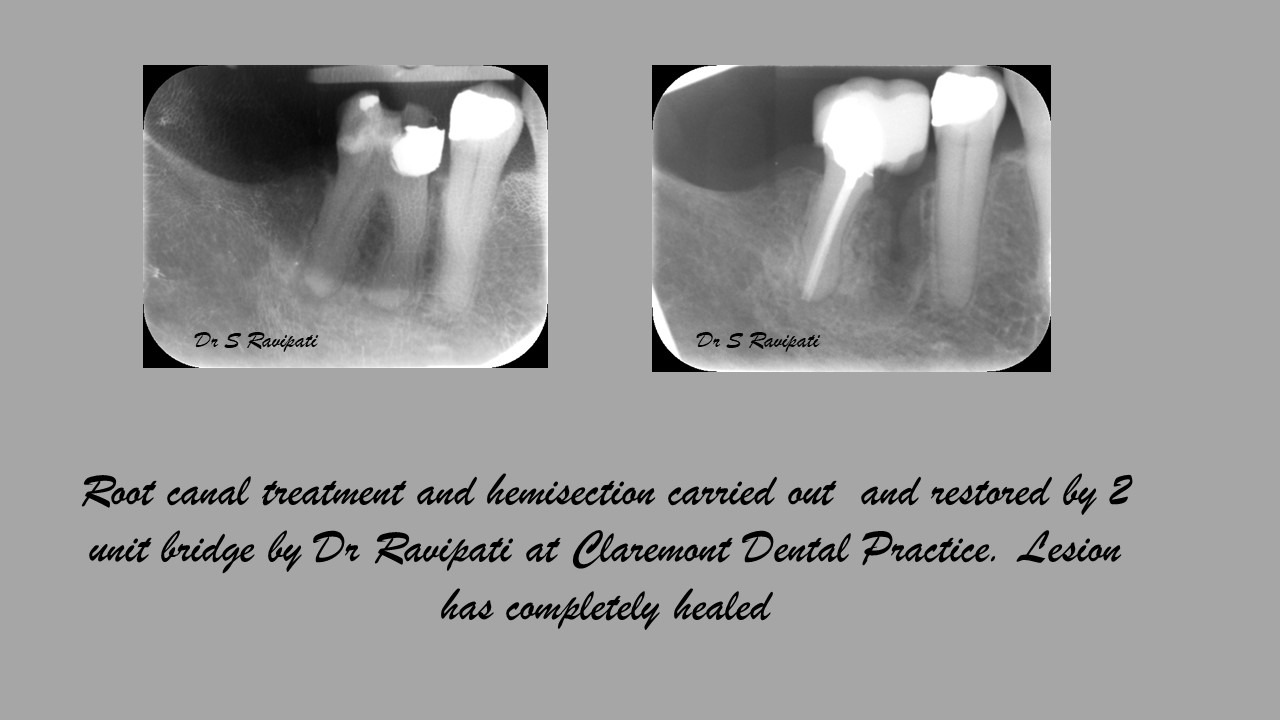

Files of different sizes are used to eliminate bacteria and infection and to shape the canals. The canals are disinfected thoroughly with irrigants and later the canals will be sealed in 3 dimensions with a special medicament called gutta-percha to prevent reinfection of the tooth and the access cavity will be sealed with a temporary filling.

After a few weeks, the tooth will be checked and when all the infection has cleared, a crown will be usually required to protect the restore the tooth to function.

Studies have shown thorough cleaning with instruments, disinfection and sealing the canals contribute to the successful healing of the infection and this success is reported as 95%.